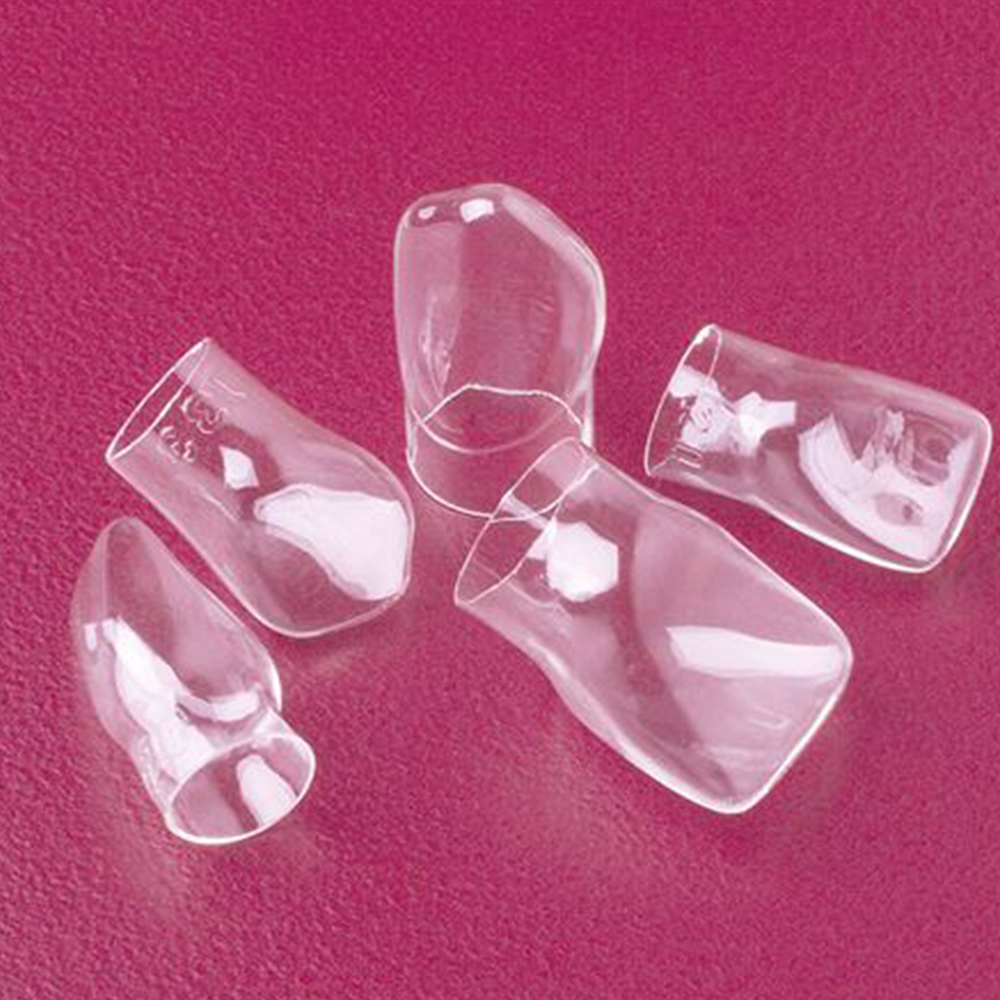

Dentalkart takes pride in its wide variety of pedo crowns, catering to the diverse requirements of dental professionals. The collection includes stainless steel crowns for primary and permanent molars, versatile polycarbonate crowns, and transparent strip crowns for anterior teeth, allowing dentists to choose the most suitable option for their young patients' specific clinical situations. With top-quality products and reliable brands, Dentalkart ensures that dental professionals can find the ideal pedo crowns to deliver exceptional care to their young patients, thus contributing to improved oral health outcomes for children.

A: Dentalkart offers a wide range of pediatric crowns, including stainless steel primary crowns, stainless steel primary molars, stainless steel permanent molars, polycarbonate crowns, and transparent strip crowns.

A: The choice of pediatric crown depends on various factors such as the tooth's position, size, and condition. Stainless steel crowns are ideal for posterior teeth, while polycarbonate crowns are suitable for anterior teeth. Transparent strip crowns are useful for esthetic concerns.